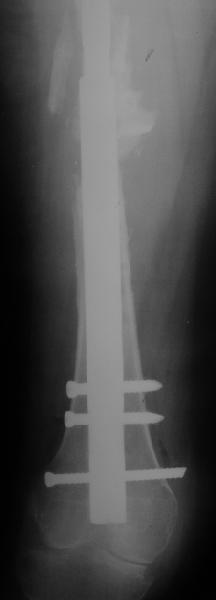

Female, rheumatoid, THA in 2003, car accident in 2006, failed plating. Nailing in Oct 2007. The nail is solid with hollow proximal part where the stem is docked. Last images are in 1 year after

nailing.

Спасибо за обсуждение. После нескольких дней тракции аппаратом сделали. Попытка закрытой репозиции не удалась из-за смещения по ширине, мешали фрагменты цемента. После их удаления репозиция получилась. Еще убрали немного цемента с ножки по латерльной стороне, чтобы обнажить 40-50 мм ее дистальной части, для плотной посадки гвоздя. Дальнейшее введение гвоздя было несложным. Протез показался нам стабильным в проксимальной части как латерально, так и медиально. Картинки в приложении.

THX for the discussion. After few days of traction by ex-fix the surgery was performed. An attempt of closed nailing was unsuccesful because of fragment translation, which was blocked by cement fragments. After removal of broken cement pieces reduction was reached "automagically". Also some cement from lateral part was removed by

chisel to expose distal 40-50 mm of the stem to allow tight fit of the nail. Further fixation by the nail was pretty easy and straightforward. Images attached. The stem looked stable in its proximal part both laterally and medially. Comments/critics are welcome.